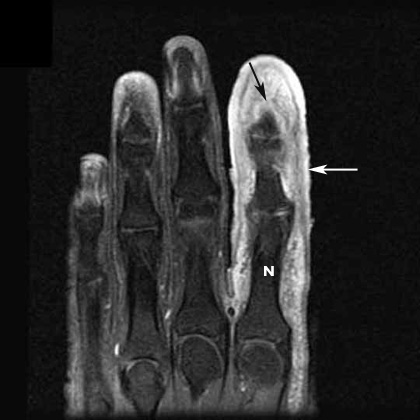

Osteomyelitis terminal phalanx of index finger

• MR exam shows soft tissue swelling and increased signal (white arrow).

• N shows normal bone signal.

• The black arrow points to increased signal in the distal portion of terminal phalanx.